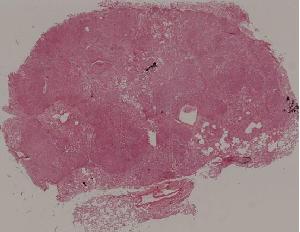

36. Lymphoma